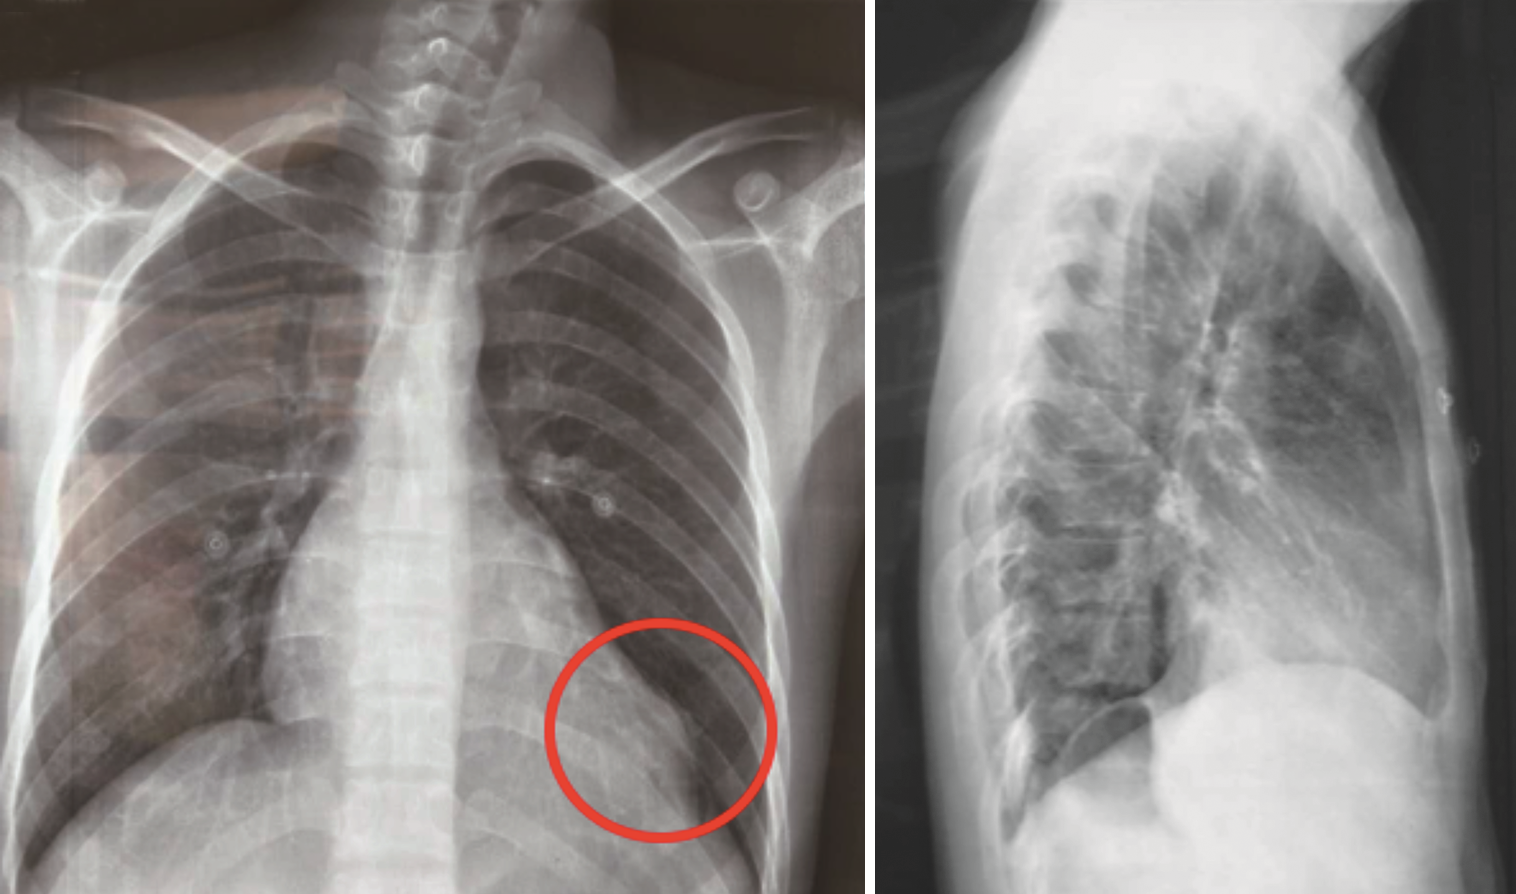

(2)胸片检查:两肺纹理大致正常,未见实变;主动脉结不宽,肺动脉段平直;左室增大,左心室下缘异常膨凸,心胸比:0.55(图1)。

院内胸片检查显示心影明显增大,形态欠规则;两肺纹理增多、模糊,左肺中下野斑片影;左侧膈肌及肋膈角显示不清,不除外左侧胸腔积液(图2)。院内胸部CT平扫检查显示心影增大,左肺中下叶可见多处斑片影,考虑肺水肿以及慢性炎症(图3)。院内心脏MRI检查显示左心室心尖部巨大瘤样膨出;冠状动脉瘤(前降支,多发)结合临床,符合白塞氏所致心脏、冠状动脉改变;肺水肿,心包积液,双侧胸腔积液,考虑心功能不全所致(图4)。